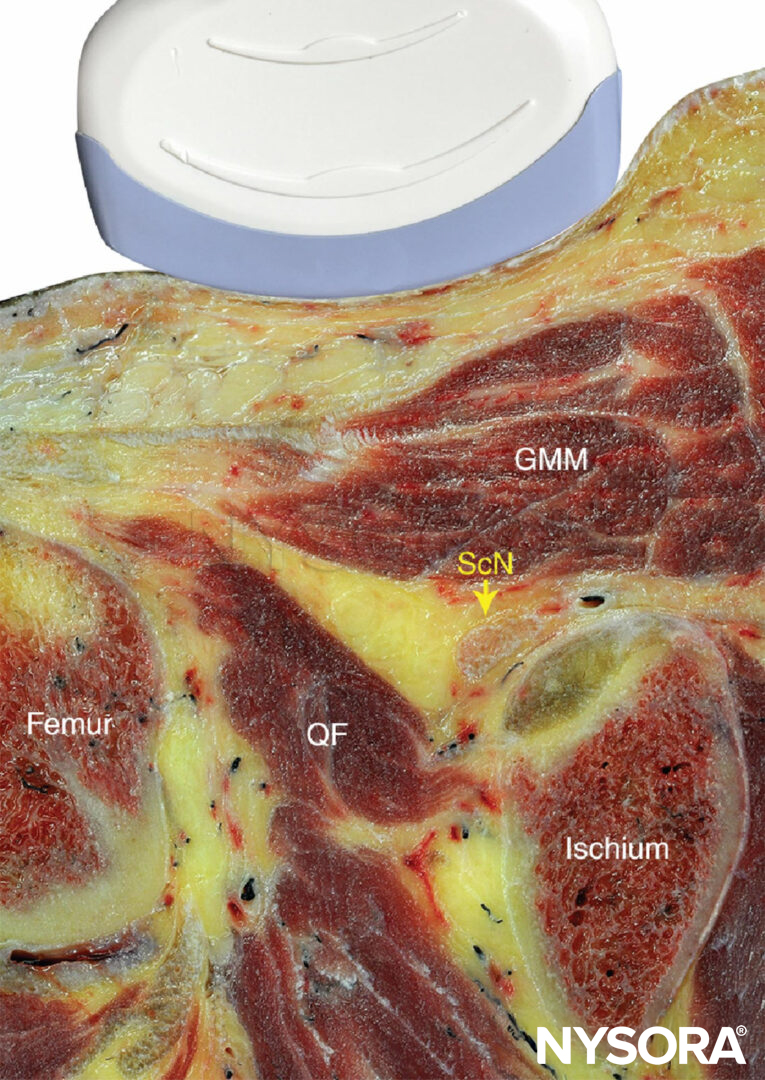

LANDMARKS AND PATIENT POSITIONING: LATERAL APPROACH

This nerve block is performed with the patient in the supine or lateral position. This can be accomplished either by resting the foot on an elevated footrest or flexing the knee while an assistant stabilizes the foot and ankle on the bed (Figure 6). If nerve stimulation is used, exposure of the calf and foot is required to observe motor responses.

This nerve block is performed with the patient in the prone or lateral position (Figure 2). A small footrest is useful to facilitate identification of a motor response if nerve stimulation is used. A footrest also relaxes the hamstring tendons, making transducer placement and manipulation easier.